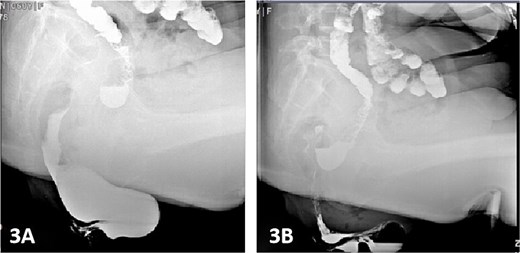

Colonic transit time assessment was performed using radiopaque markers. At 24 h post-ingestion, 19 markers were retained within the colon, with complete clearance observed at 48 and 72 h, confirming normal colonic motility (Fig. 2). Defecography demonstrated a Grade III RC, characterized by a maximal depth of 76 mm during straining and persistent barium retention post-evacuation, consistent with obstructed defecation syndrome (ODS) (Fig. 3).

Postoperatively, the patient was administered intravenous cefuroxime and metronidazole for 3 days as prophylactic antimicrobial therapy. The iodine-impregnated vaginal gauze pack and indwelling urinary catheter were removed 24 h after surgery. Daily vaginal dressing changes were performed, involving thorough wound disinfection with povidone-iodine. In cases of excessive vaginal discharge, additional irrigation with normal saline was conducted. The interrupted silk sutures on the posterior vaginal wall were removed during a follow-up visit 2 weeks postoperatively. At 15 days postoperatively, following suture removal, repeat defecography demonstrated a residual RC depth of 11 mm, with complete resolution of the patient’s defecatory dysfunction (Fig. 5). During the 24-month postoperative follow-up period, the patient maintained normal defecatory function with no recurrence of obstructive symptoms. However, repeat defecography was not performed due to the patient’s personal preference.

Postoperative defecography at 15 days, the image demonstrates a residual RC depth of 11 mm.